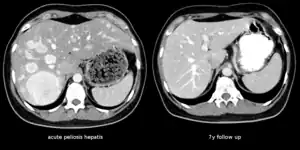

| The CT scan of a patient with peliosis hepatis (left): The follow-up CT (right) after 7 years shows full remission. | |

Treatment is usually directed towards management of the underlying cause. Withdrawal of azathioprine leads to remission in kidney transplant; bacillary peliosis responds to antibiotics. In rare circumstances partial resection of liver or transplant may be required.